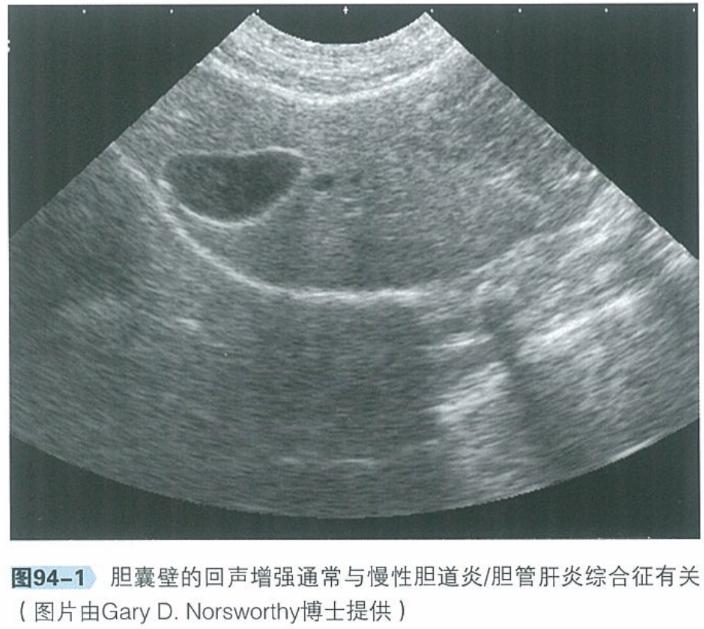

b.腹部超声:腹部超声是检查肝脏、胆管系统及胰腺实质结构极为有用的工具。肝脏回声通常正常,胆管及胆囊可见异常,包括胆总管、胆囊或肝内胆管扩张、部分或完全阻塞,胆汁淤积。